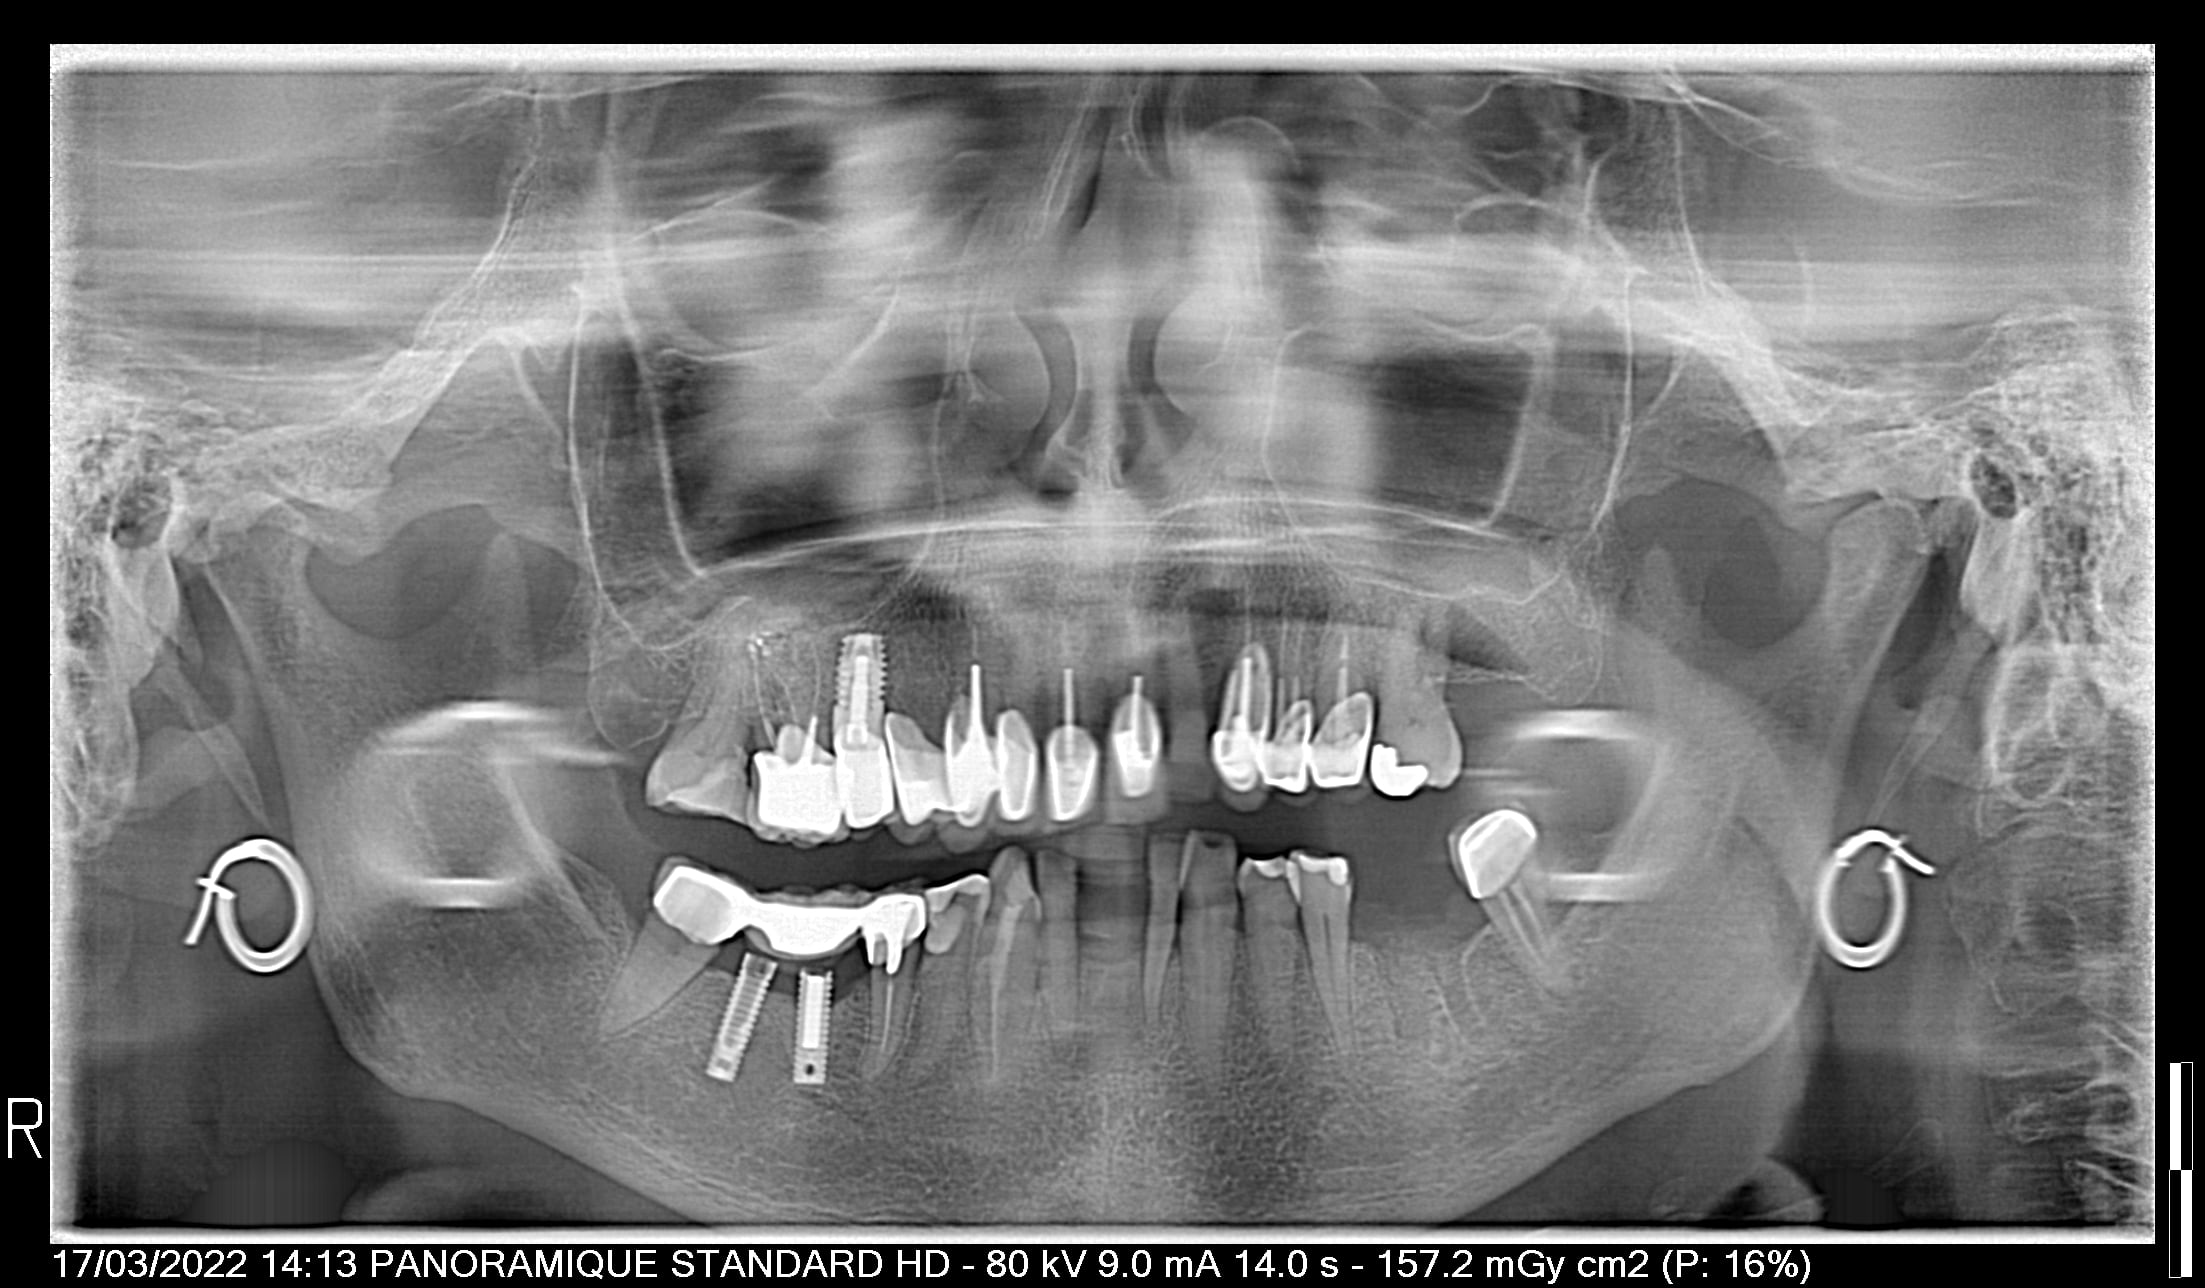

qui peut me dire la marque de ces implants foireux??

Inlay core sur implants.... concept intéressant 😄

J'aime bien les deux implants non connectés sous l'inter de bridge dentoporté...

bon mais ça me dit pas c'est quoi la marque de l'implant (vous aurez noté la fracture du col sur l'implant sur larétroalvéolaire!!) c'est la mère et la fille charcutées par le même dentiste..

de grandes chances que çà soit du sterioss

https://www.spotimplant.com/fr/implants-dentaire/steri-oss/steri-oss-original-non-hex

et vu l'état...., c'est trèpan => poubelle d'autant que tu peux toujours te gratter pour avoir des pèces prothétiques....